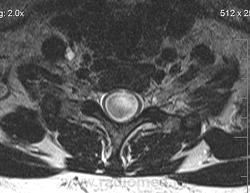

Сирингомиелия шейно-грудной локализации? Аномалия Арнольда-Киари I. Платибазия.

здоровенная сирингогидромиелитическая киста (по видимому, "высокого давления"), мальформация Киари 1.   также имеются признаки внутренней окклюзионной гидроцефалии.